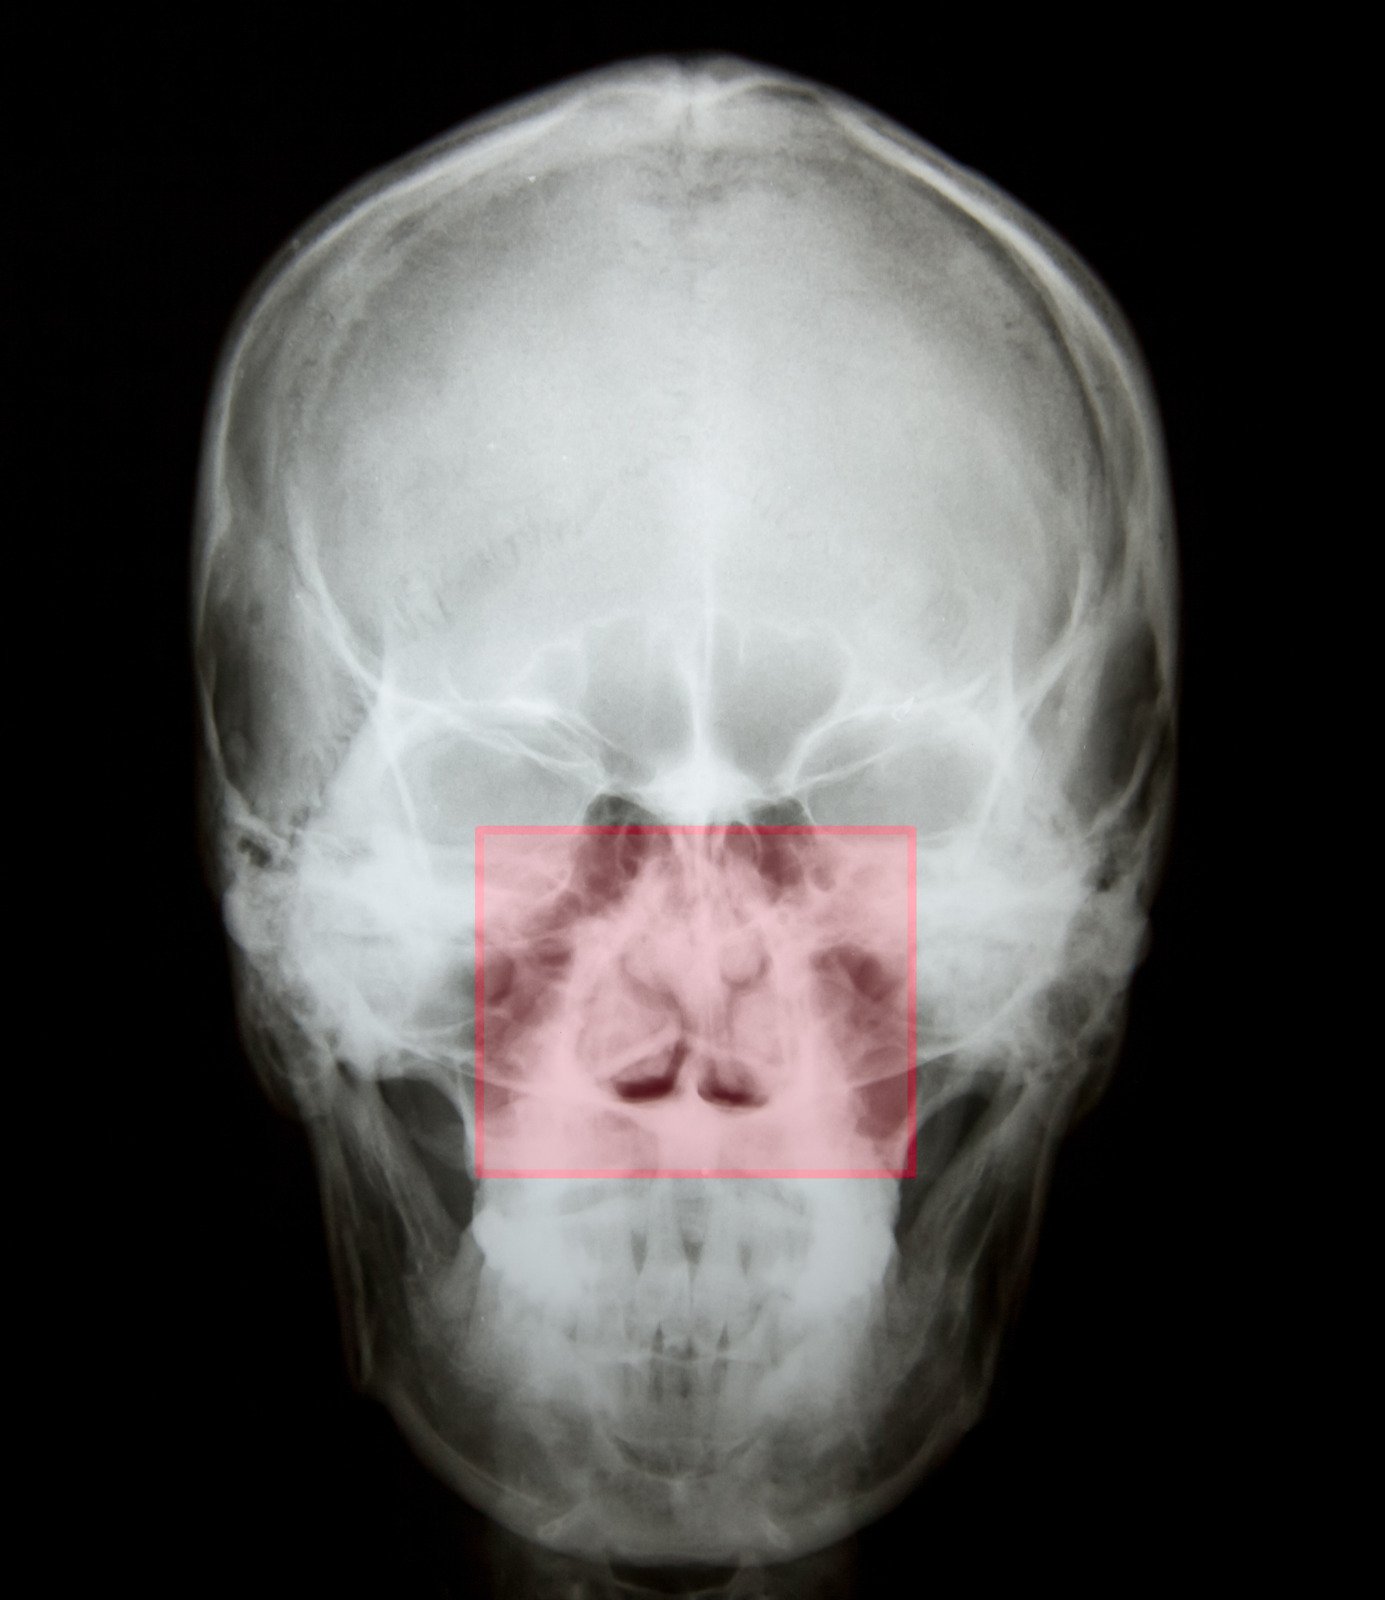

비경검사(Nasal Endoscopy), CT 스캔 등을 통해 비중격의 상태와 코 내부 구조를 평가.